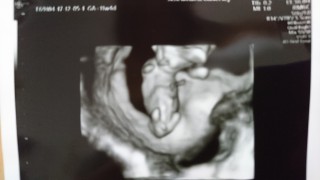

2週間ぶりの健診。無事に育っていてくれてうれしい(>ω<) 性別はまだわからないと思っていたら、なんとこの日に判明!まだ確定ではないけれど待望の男の子(^^)足の間にシンボルもちゃんと写っていました!こんなに早くにわかるんですね。